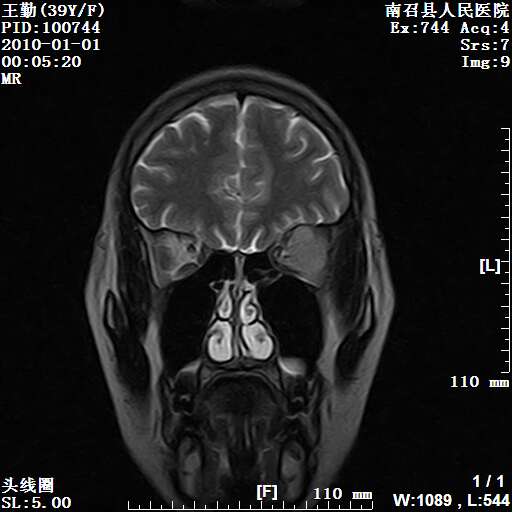

以下是引用随光逐影在2010-1-22 9:03:00的发言:[br]考虑左侧中颅窝(蝶骨翼区)脑膜瘤侵犯蝶骨翼并突入左侧眼眶。

以下是引用水过无痕在2010-1-22 14:55:00的发言:[br]一、定位:颅外占位;二、定性:恶性可能性大;三、组织来源:来源于左侧眼外直肌或其他部位;考虑为:横纹肌肉瘤>转移瘤>脑膜瘤.